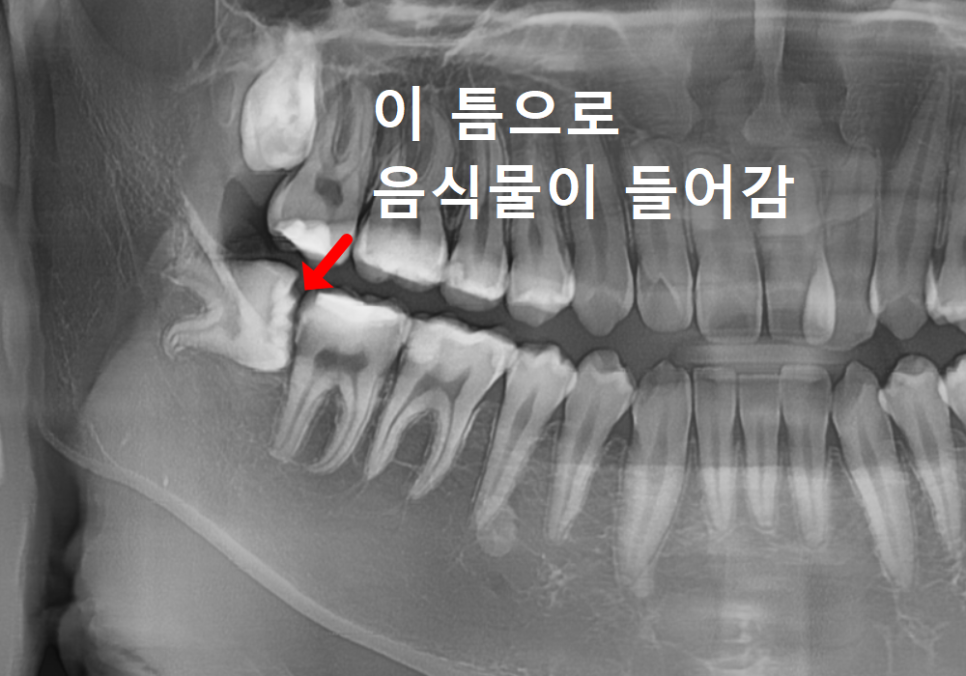

하지만 엑스레이를 찍어보니

상황이 조금 달랐습니다.

사랑니가 앞 치아(#47) 쪽으로

비스듬히 누워 있는 상태였거든요.

여기서 꼭 아셔야 할 점이 있어요.

사랑니가 잇몸 속에 아예 푹 잠겨 있으면

오히려 괜찮습니다.

하지만 아주 조금이라도

잇몸 밖으로 고개를 내밀면,

앞 치아와 사랑니 사이에 좁은 틈이 생기죠.

이 틈은 칫솔질을 아무리 열심히 해도

칫솔이 닿지 않는 '사각지대'가 됩니다.

음식물 찌꺼기와 세균이 머물기

딱 좋은 환경이 되는 거예요.

그래서 잇몸 밖으로 드러난 사랑니는

웬만하면 뽑는 게 좋습니다.